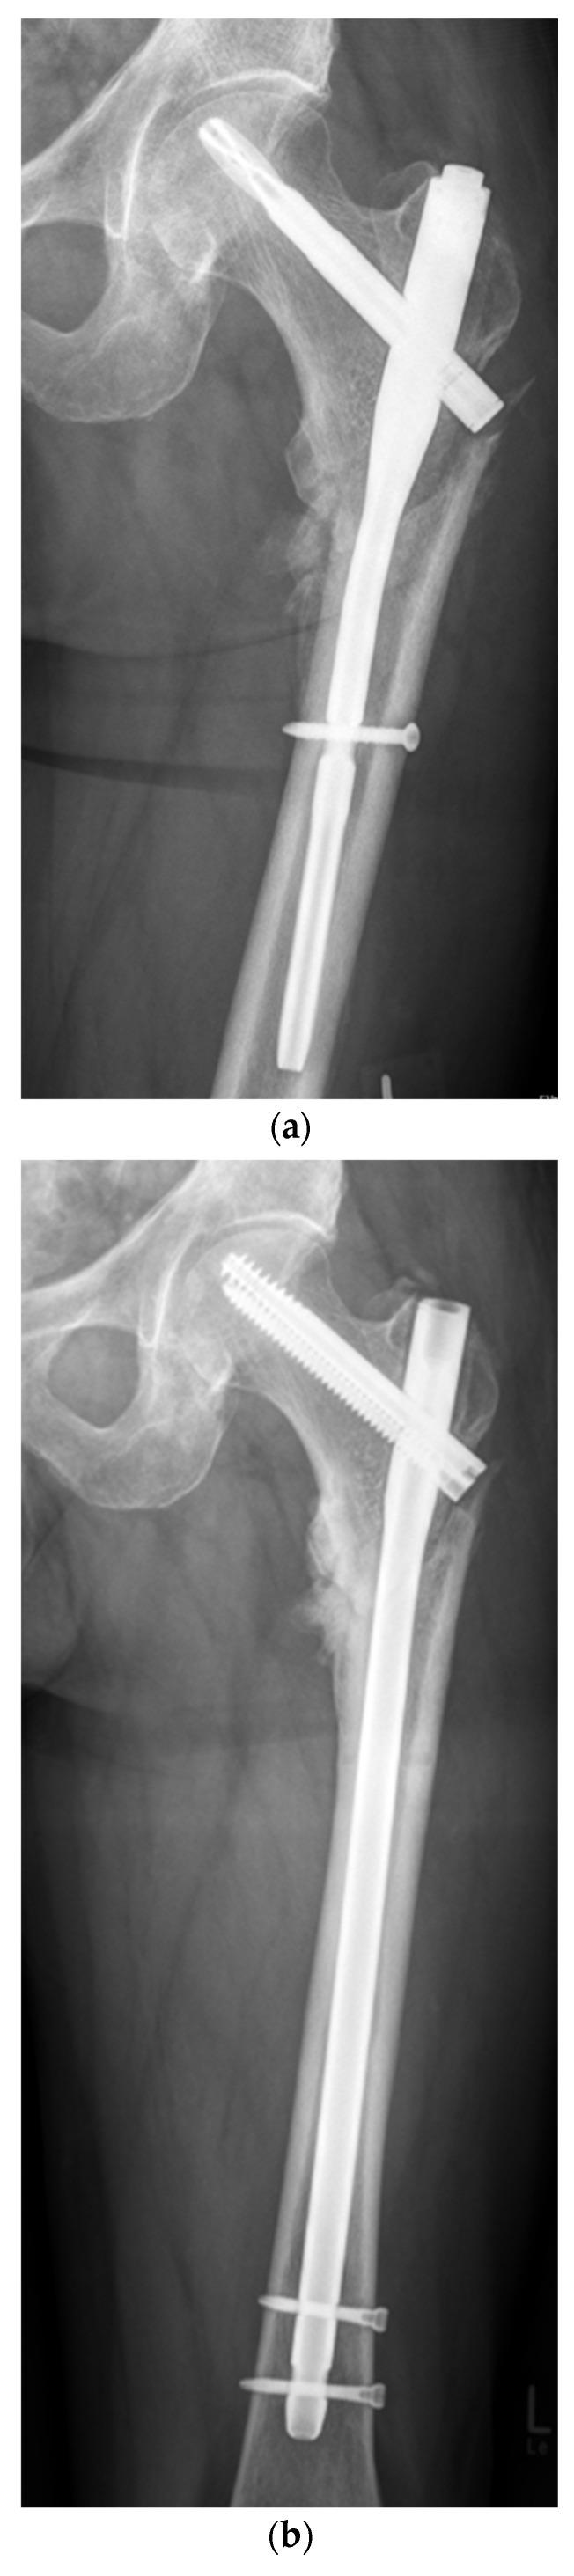

Trochanteric and subtrochanteric fractures result in nonunion in more than 20% of cases. The aim of this study was to assess the functional and radiological results following revision cephalomedullary nailing and 95-degree angled blade plating in aseptic trochanteric and subtrochanteric nonunion. In a retrospective multi-center study between January 2010 and December 2020, a total of 68 consecutive patients (21 women and 47 men) from two European level I trauma centers with the diagnosis of aseptic nonunion were recruited. Follow-up assessment and the patients' convenience were assessed using the Harris Hip Score, Visual Analog Scale for pain at rest and on stress/exertion and Short Form-12. The patients' mean age was 57 (range 26-85) years. After a follow-up period of 12 months, one case of persistent nonunion in the cephalomedullary nail group and 10 cases in the blade plate group were identified. The mean duration of surgery was 137 ± 47 min in the cephalomedullary nail group and 202 ± 59 min in the blade plate group (<0.0001). Short-term postoperative complications included wound dehiscence, bleeding, mismatched screw and hematoma. The mid-term results 12 months after surgical revision demonstrated significantly different osseous union rates ( = 0.018). The long-term functional outcome according to the Harris Hip Score 6 years (range 2-10) after revision surgery demonstrated 81 ± 21 points in the cephalomedullary nail group and 64 ± 23 points in the plate group ( = 0.026). This study demonstrated that the revision treatment of trochanteric and subtrochanteric nonunion using a 95-degree blade plate or cephalomedullary nail resulted in a high percentage of osseous union, with a low incidence of complications and good functional results for both methods.

转子间骨折和转子下骨折病例中超过20%会发生骨不连。本研究的目的是评估在无菌性转子间和转子下骨不连患者中,采用翻修髓内钉和95度角钢板固定后的功能和影像学结果。在一项回顾性多中心研究中,于2010年1月至2020年12月期间,从两个欧洲一级创伤中心连续招募了68例诊断为无菌性骨不连的患者(21例女性和47例男性)。使用Harris髋关节评分、静息和应力/活动时疼痛的视觉模拟量表以及简明健康调查问卷12项来评估随访情况和患者的便利性。患者的平均年龄为57岁(范围26 - 85岁)。在12个月的随访期后,髓内钉组发现1例持续性骨不连,钢板组发现10例。髓内钉组的平均手术时长为137 ± 47分钟,钢板组为202 ± 59分钟(<0.0001)。术后短期并发症包括伤口裂开、出血、螺钉不匹配和血肿。手术翻修12个月后的中期结果显示骨愈合率有显著差异(= 0.018)。根据Harris髋关节评分,翻修手术后6年(范围2 - 10年)的长期功能结果显示,髓内钉组为81 ± 21分,钢板组为64 ± 23分(= 0.026)。本研究表明,采用95度角钢板或髓内钉对转子间和转子下骨不连进行翻修治疗,两种方法的骨愈合率都很高,并发症发生率低,功能结果良好。